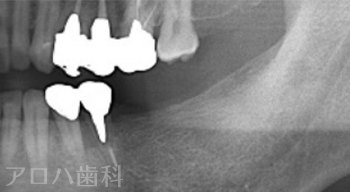

CASE01

初診時

治療終了後5年時

| 主訴 | 入れ歯をやり替えたい |

|---|---|

| 治療内容 | 上下顎とも状態が悪い歯を抜いて奥歯をインプラントで修復しました。 前歯は患者さまの希望のもとそのままにしています。 上顎は骨の高さが足りなかったため、【サイナスリフト】という特殊な手術を行い骨の高さを獲得しています。 術後経過もメインテナンスに通っていただいており、良好な状態を保っています。 |

| 治療期間 | 1年6ヶ月 |

| 治療費用 | 5,060,000円 |

| 費用詳細 | ・サイナスリフト(2か所) 660,000円 ・セデーション(静脈内鎮静法) 110,000円 ・TEC(仮歯) 220,000円 ・インプラント手術+アバットメント+上部構造(9歯) 3,960,000円 ・ポンティック(1歯) 110,000円 |